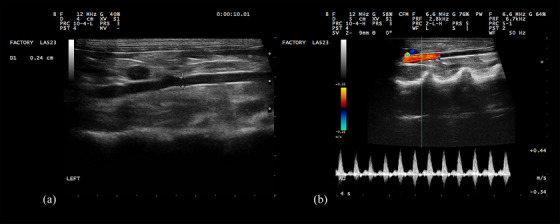

Methods: Sixty healthy adult male mixed-breed rabbits underwent ultrasonographic evaluation. Renal cortical thickness and abdominal aortic diameter were measured, ensuring that only rabbits without clinical or ultrasonographic signs of kidney disease were included.

Results: Pearson correlation analysis revealed a positive correlation between renal cortical thickness, aortic diameter and body weight. However, the ratio of renal cortical thickness to aortic diameter remained independent of body weight.

Conclusions: This study established a normative reference range for renal cortical thickness relative to aortic diameter in rabbits, providing a novel diagnostic parameter for renal assessment. The confidence intervals for the ratio were 0.82 (0.77-0.87) to 1.35 (1.30-1.40) for the left kidney and 0.79 (0.74-0.84) to 1.33 (1.27-1.38) for the right kidney, marking the first report of this method in the literature.